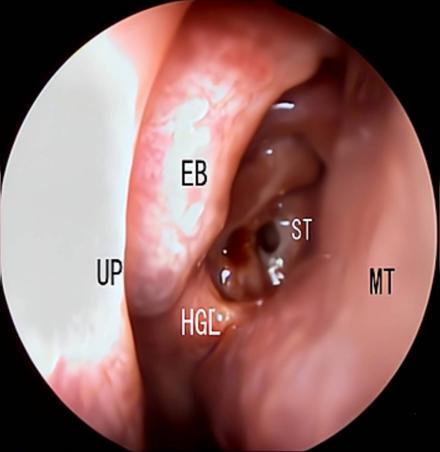

摘要:目的 探究经中鼻甲基板入路的手术技巧及临床效果,旨在系统评估一种兼具良好手术视野和微创性的蝶窦开放径路。方法 回顾性分析2019年9月-2023年9月该院收治的35例孤立性蝶窦病变或单侧蝶窦伴毗邻筛窦受累患者的临床资料,均经中鼻甲基板入路的“四步”程序化操作开放蝶窦。观察手术相关情况和并发症发生情况;采用视觉模拟评分法(VAS)评分,评估头痛和流涕等症状改善情况;采用改良隆德-肯尼迪(MLK)评分,评价术腔恢复状况。结果 所有患者术中保留钩突、中鼻甲和筛泡,26例(74.3%)保留上鼻甲;所有患者均达到临床治愈标准,表现为:术腔引流通畅,黏膜完全上皮化,以及蝶窦开口维持良好开放状态。术后病理显示:蝶窦霉菌病19例(54.3%),蝶窦息肉7例(20.0%),蝶窦黏膜慢性炎症9例(25.7%)。所有患者均未发生严重并发症,仅1例(2.9%)于术后12 d出现中鼻甲创面渗血,经电凝止血后治愈。头痛VAS评分由术前的(4.71±1.66)分,降至术后的(0.83±0.39)分,手术前后比较,差异有统计学意义(t = 13.71,P < 0.01);流涕VAS评分由术前的4.00(0.00,6.00)分,降至术后的0.00(0.00,1.00)分,手术前后比较,差异有统计学意义(Z = -4.47,P < 0.01);手术前后嗅觉减退VAS评分比较,差异无统计学意义(P > 0.05)。MLK评分由术前的4.50(2.00,4.00)分降至1.00(0.00,1.00)分,手术前后比较,差异有统计学意义(Z = -5.20,P < 0.01)。结论 经中鼻甲基板入路蝶窦开放术,严格遵循鼻窦解剖层次,在最大限度地保留鼻腔生理结构的前提下,可获得理想的术野暴露。该术式对于局限于蝶窦及后组筛窦的病变,具有确切的临床疗效。值得应用于临床。